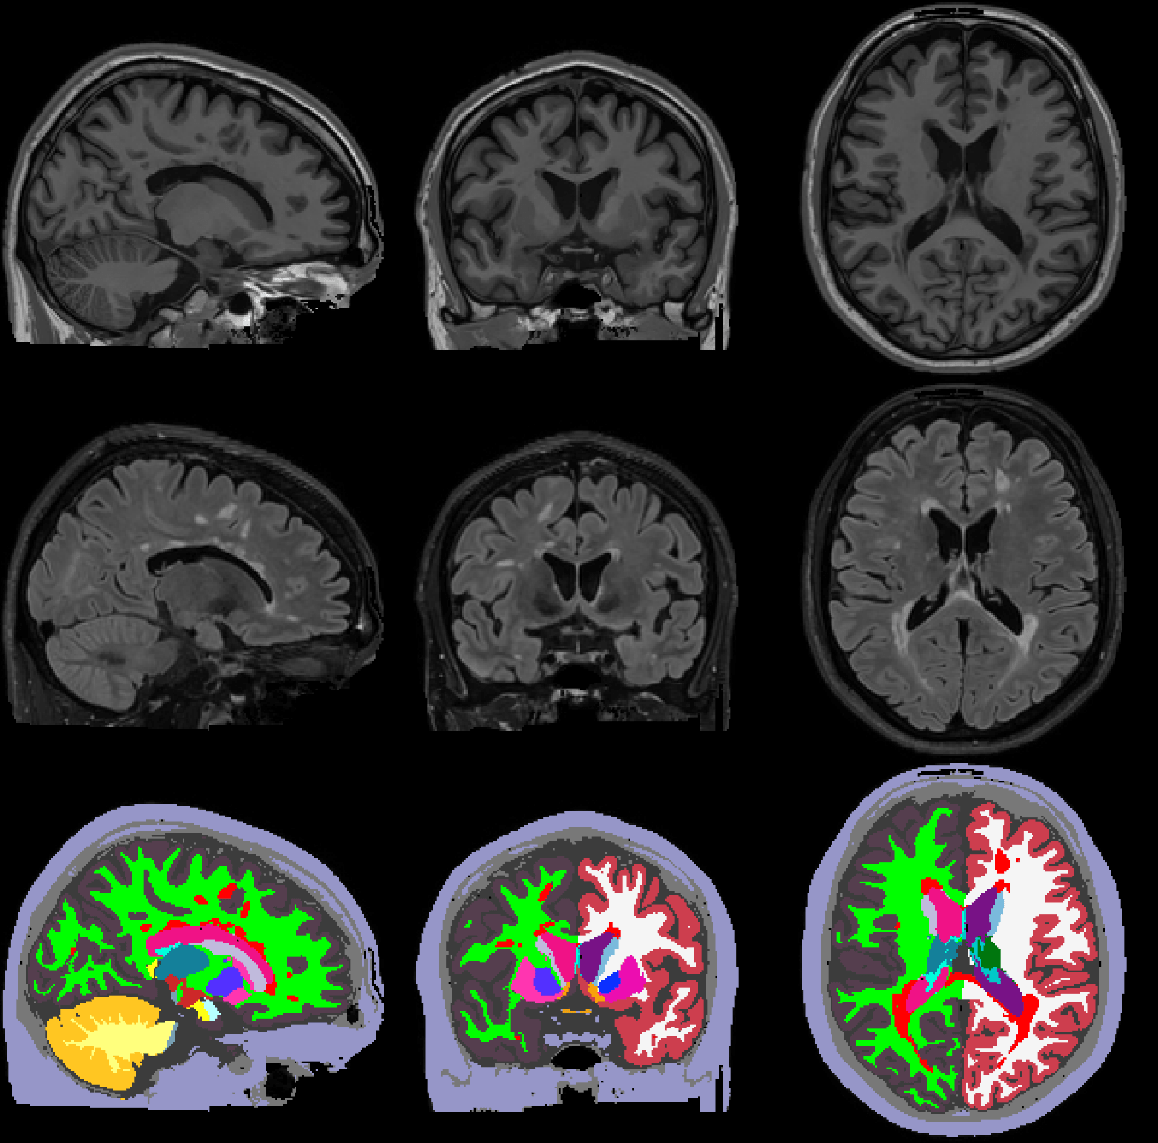

In a previous post, I described how to obtain brain segmentations using a Gaussian Mixture Model (GMM). One of the limitations of this brain segmentation